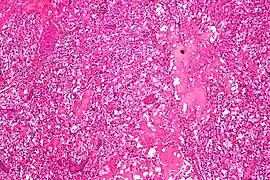

| Micrograph of a cerebellar hemangioblastoma. HPS stain. | |

Micrograph of cerebellar hemangioblastoma. HPS stain. -

Micrograph of cerebellar hemangioblastoma. HPS stain.